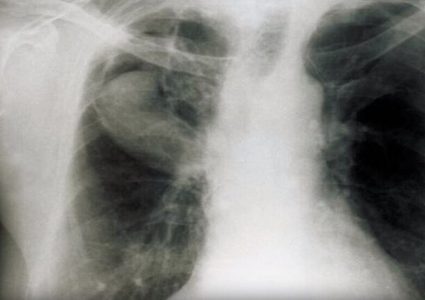

أكدت السلطات الصحية الصينية ارتفاع حصيلة ضحايا فيروس كورونا إلى 170 حالة وفاة، وذلك بعد وفاة 37 شخصا آخرين متأثرين بإصابتهم بالفيروس القاتل في مقاطعة …

اكتشف علماء جامعة “Chengdu” نوعين جديدين من البكتيريا القاتلة المقاومة للمضادات الحيوية في دم المرضى بالصين. وتبين أن مريضين كانا يحملان نوعا غير محدد من …